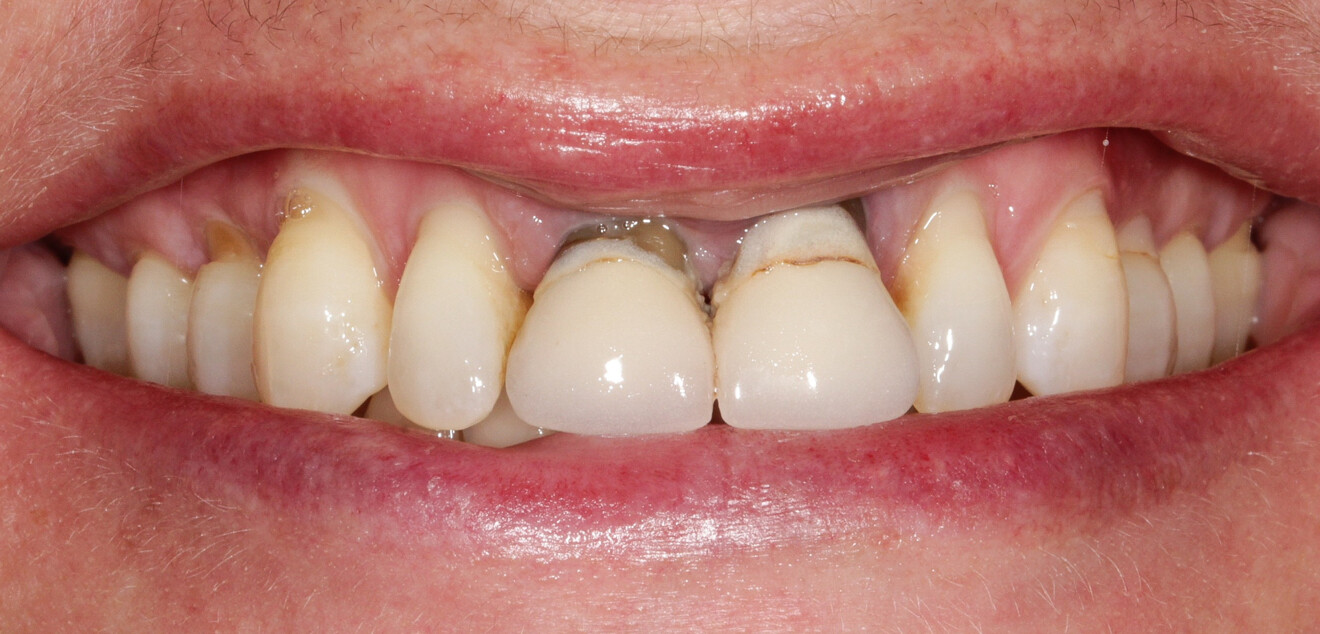

Une patiente de 49 ans nous a été adressée par l’un de nos confrères pour le remplacement de ses quatre incisives maxillaires (Fig. 23). Dans un contexte parodontal avancé, ses incisives centrales présentent une mobilité terminale (classe IV) elle n’ose plus les brosser de peur de les perdre lors de la manoeuvre. La patiente ne présente pas de problèmes de santé particuliers.

À l’examen, on observe une mobilité des quatre incisives maxillaires, une insuffisance osseuse verticale et horizontale, associées notamment au niveau de 11 et 21, la présence de plaque, de tartre et d’inflammation gingivale, surtout au niveau du bloc antérieur maxillaire. On note également la présence d’une dent de sagesse (dent 18) perdue (Figs. 24–26).